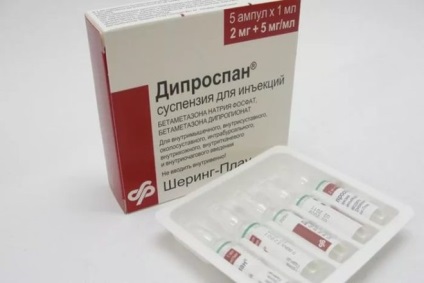

- Glucocorticoizii. Medicamentele din acest grup elimina inflamatia.